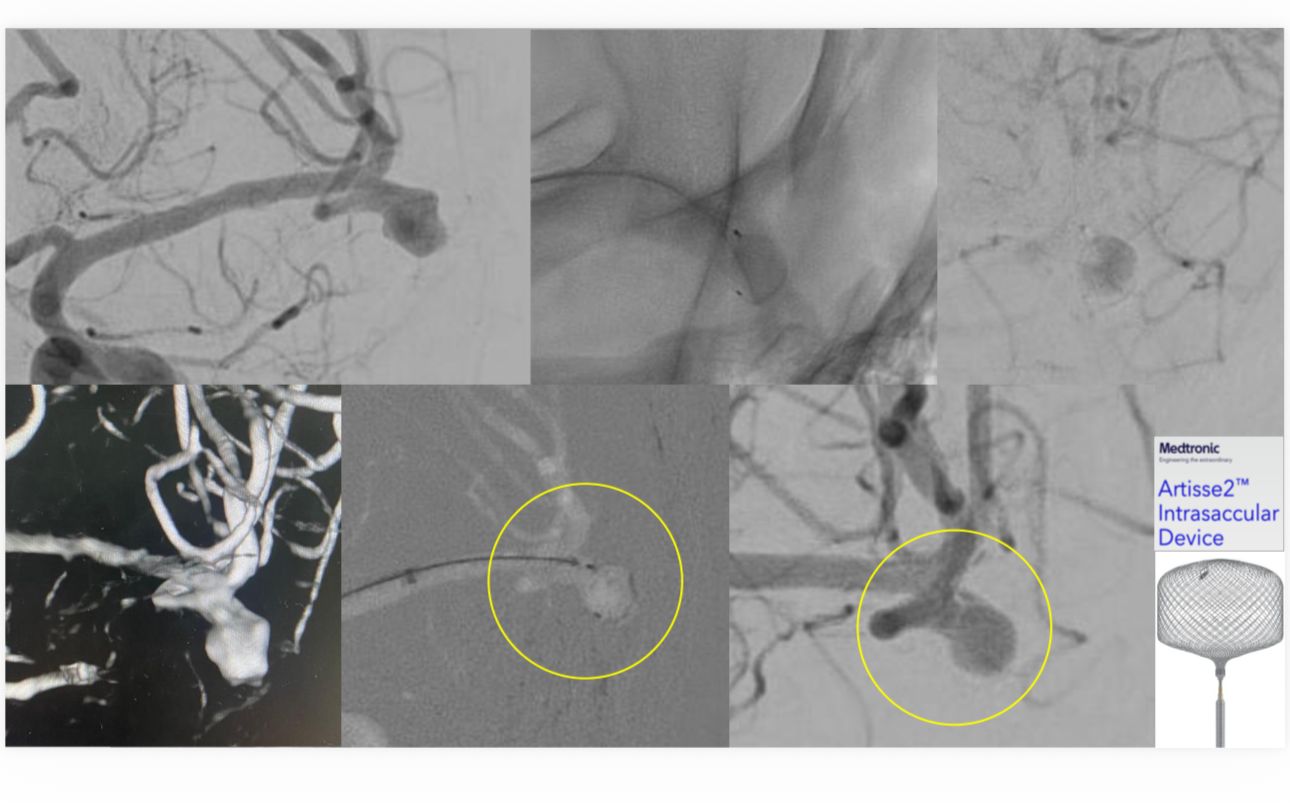

نجاح علاج مريض بتمدد شرياني دماغي في جامعي الخبر